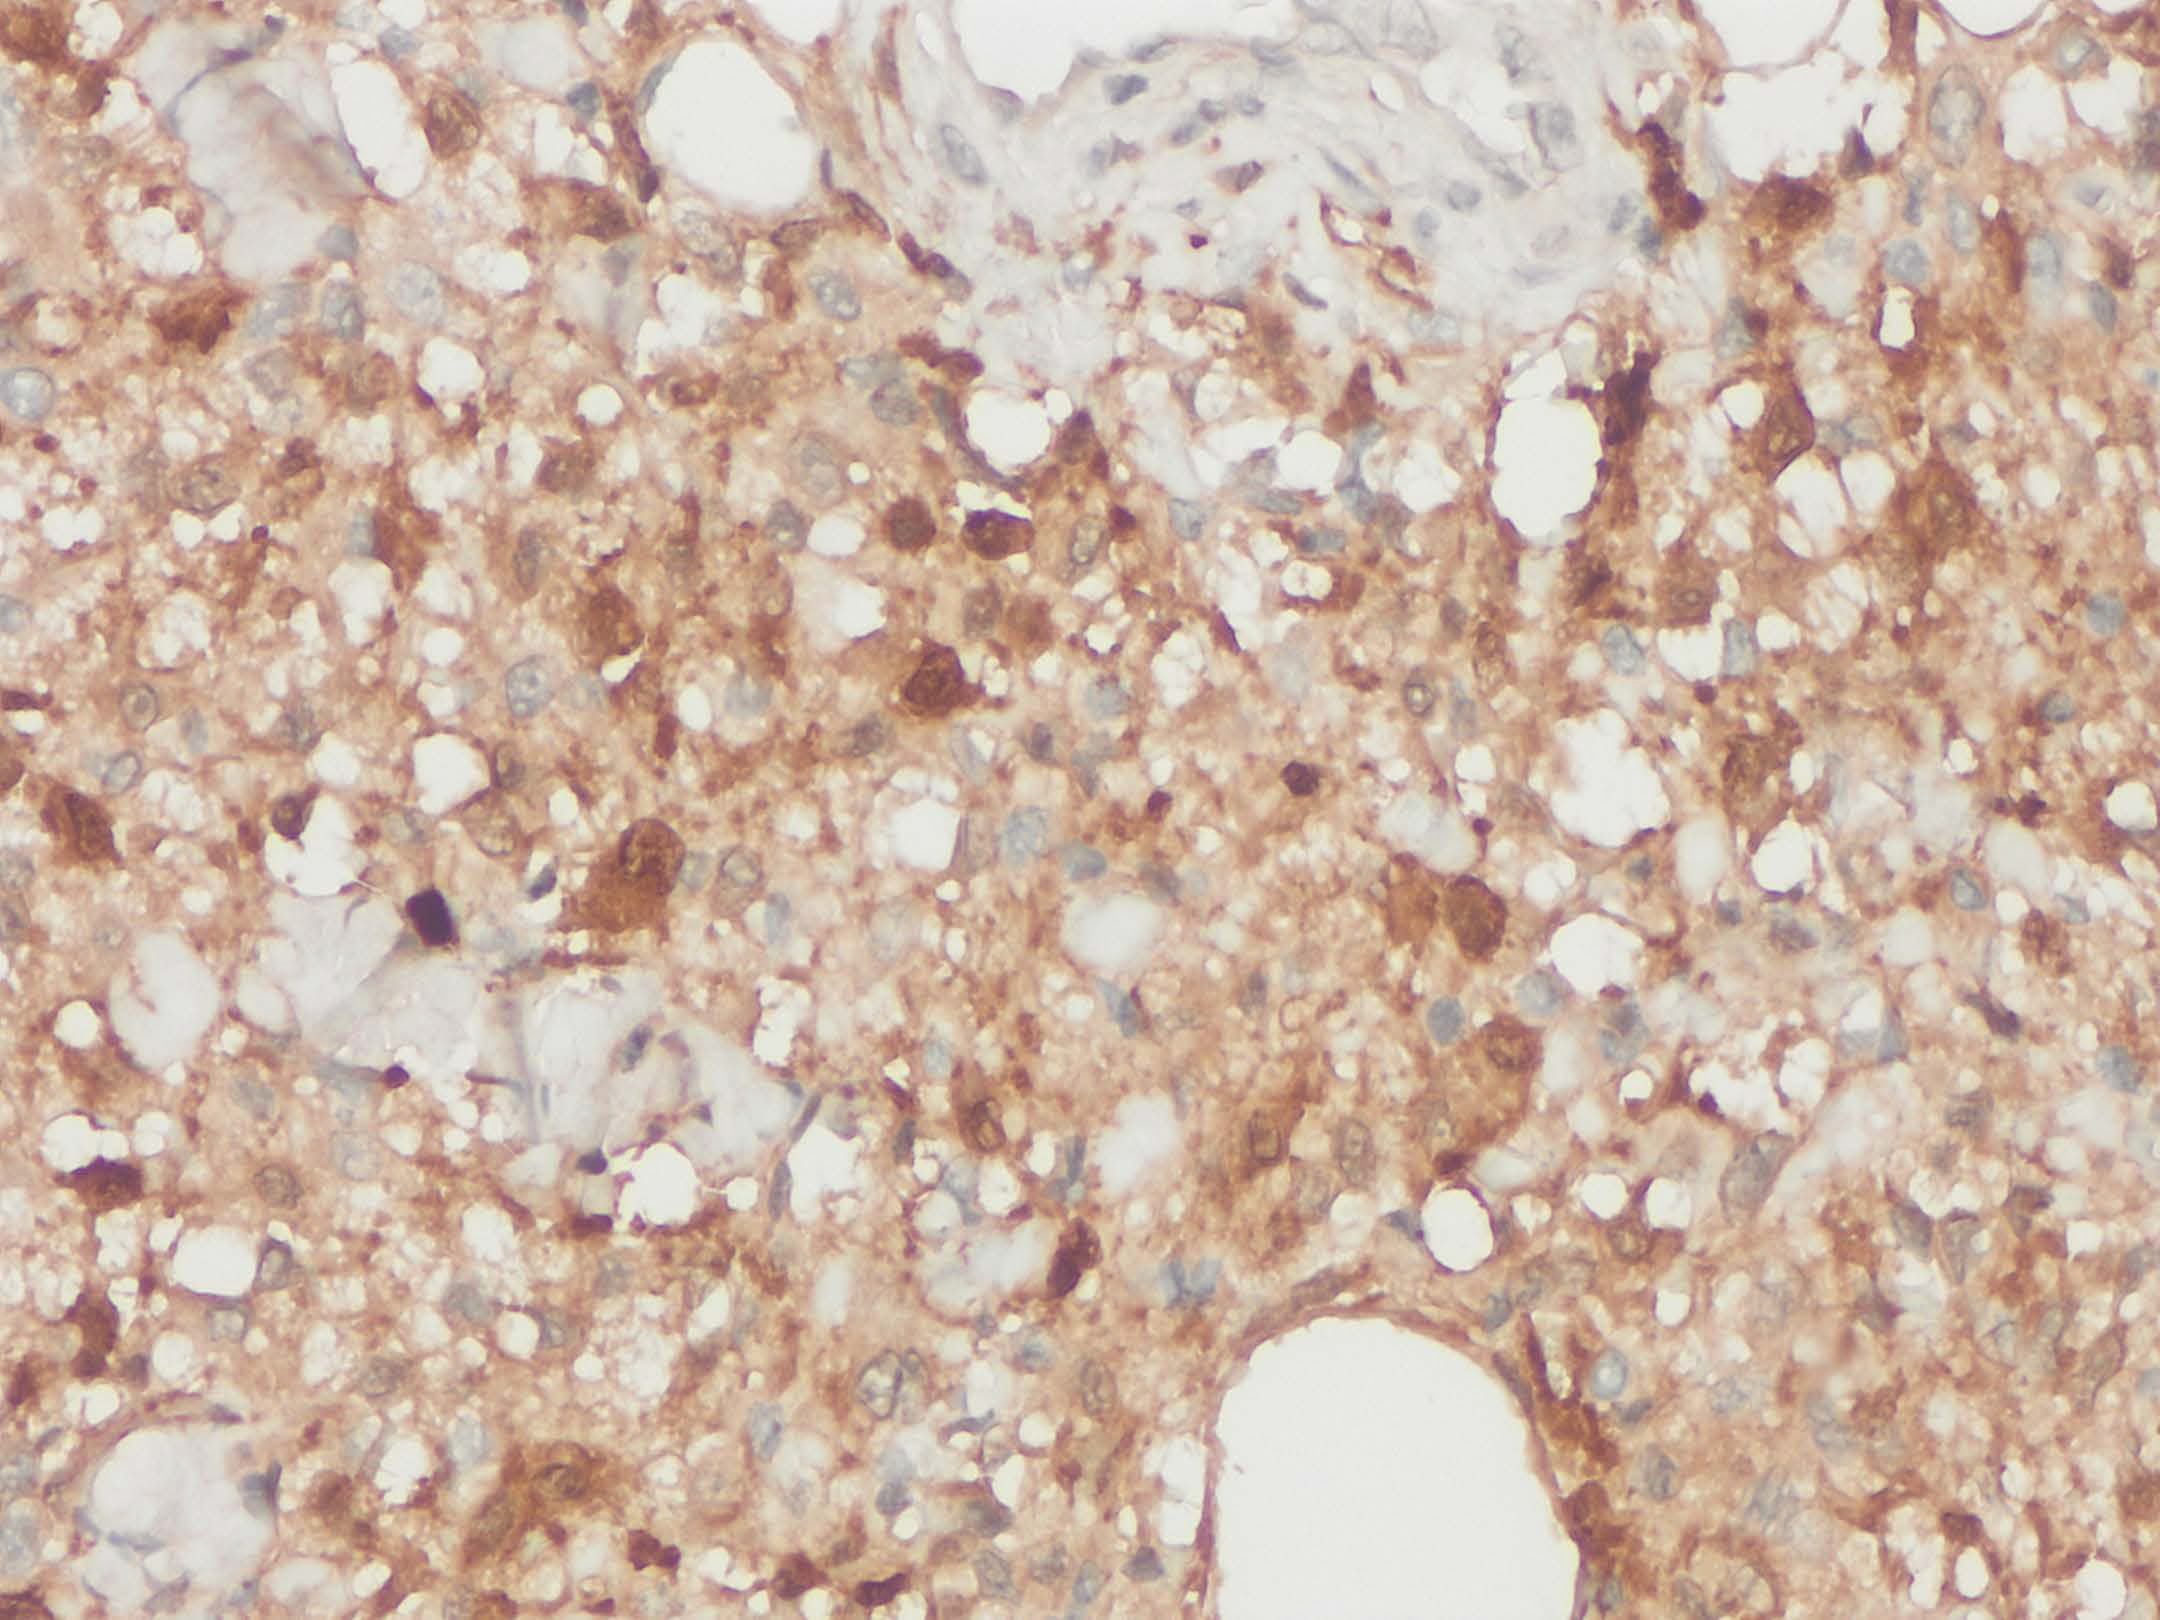

A 60 year-old male presented with multiple skin lesions which was biopsied (figure). Wokup revealed the lesional cells positive for OCT2, CD68, & negative for MelanA/HMB45/SOX10.

This is a case of Rosai-Dorfman Disease (RDD) that are characterized by enlarged round to oval nuclei, pale chromatin, conspicuous nucleoli, and abundant pale eosinophilic cytoplasm. By immunohistochemistry, the RDD cells are positive for histiocytic markers (CD68, CD163), S100, and OCT2. Approximately 50% of these RDD cases harbor MAPK pathway gene mutations, most common being KRAS, NRAS and MAP2K1 (PMID: 37167084).